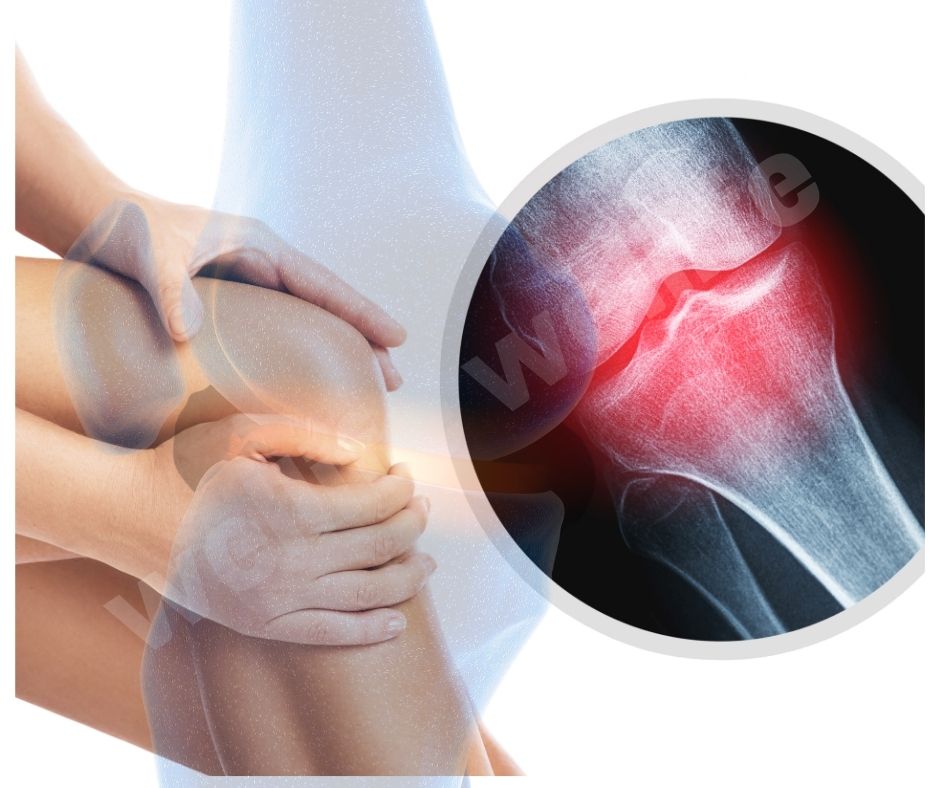

2022년에 발표된 연구에서는 콘드로이친이 관절 보호 효과를 강화하는 데도 중요한 역할을 한다는 결과가 나왔습니다. 이는 특히 무릎 관절에 좋은 영향을 미친다고 합니다 .